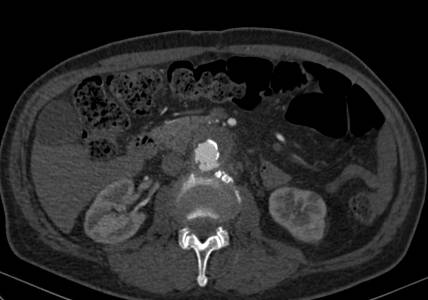

Paciente da entrada hospitalar com dor cardíaca típica sendo diagnosticado com infarto agudo do miocárdio em dezembro de 2019. Apresentava passado de outros três episódios e de revascularização cardíaca com mamária e ponte de safena. Durante internamento paciente evolui com dor abdominal importante sendo indicada realização de tomografia de abdome total que indicou a presença de hematoma intramural da aorta abdominal.

O estudo de angiotomografia evidenciou que as artérias iliacas externas e femorais apresentavam-se com muitas calcificações e ponto de estenose mais crítica em artéria ilíaca comum direita. Diante dos achados de imagem, foi optado por endoprotese de aorta abdominal de baixo perfil (Incraft – Cordis).